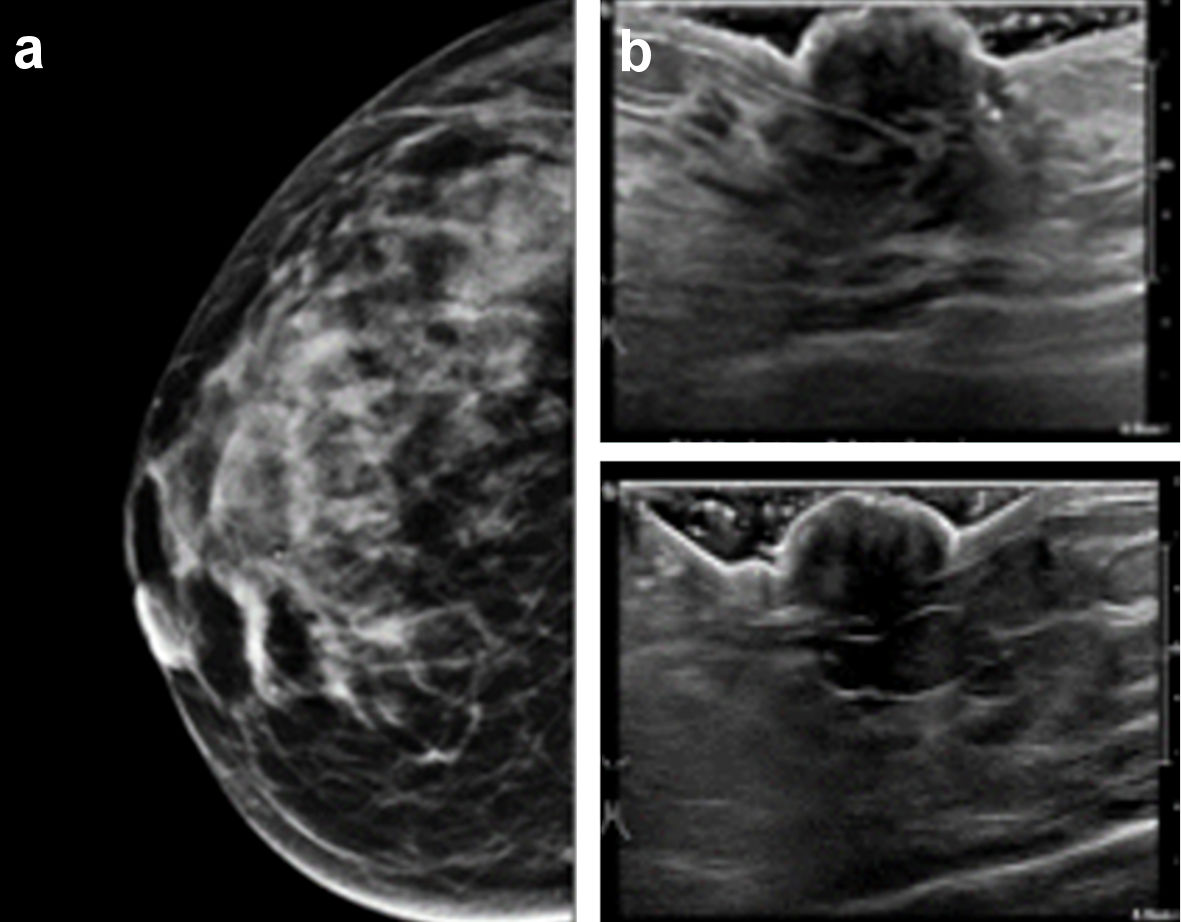

Mammography and targeted ultrasound were unremarkable (Fig. 2a, b). Breast magnetic resonance imaging (MRI) showed asymmetric enhancement of the right nipple (Fig. 3). Nipple excision vs. fine needle aspiration vs. incisional nipple biopsy were reviewed with the patient. After almost 2 years of watchful waiting and expectant management patient with ongoing complaints of nipple pain, she elected for excisional biopsy of her right nipple. Preoperatively, she met with plastic surgery to discuss delayed reconstruction.

![]() Click for large image | Figure 2. (a) Mammography of the right breast. No retro-areolar calcifications nor abnormalities were seen on regular or magnified views. (b) Ultrasonography of the right nipple. No retro-areolar masses or abnormalities were seen. |

Mammogram findings ranged from normal, to nonspecific, to variably sized calcifications or asymmetry at the nipple-areolar complex or subareolar region. Ultrasound often confirmed the mammographic findings and noted irregularly outlined nodules in the subareolar region of the nipple. One study reported an irregular mass with enhancement on contrast computed tomography (CT), suspicious for malignancy [10]. Only one report noted MRI findings, an irregular mass in the subareolar region of the nipple [11]. Our patient’s breast MRI, related to the symptomatic nipple, noted asymmetric enhancement of the right nipple. This review reveals that imaging of SyT cannot distinguish it from other neoplasms and cannot be trusted to distinguish SyT from carcinoma of the breast.